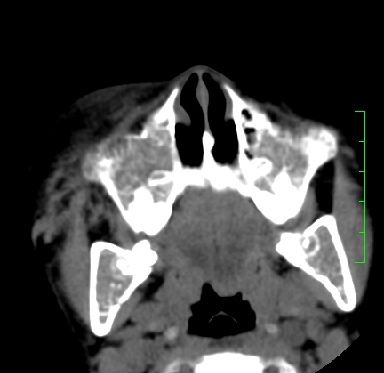

标题: PED1889:上颌窦病变

m,10y,外伤做ct

骨纤?

支持;骨纤,有皮肤色素沉着,性早熟时为albright综合征。

霉菌性鼻窦炎

骨化性纤维瘤可能性大。(与骨纤的鉴别:常见于面颅骨,多骨发病)